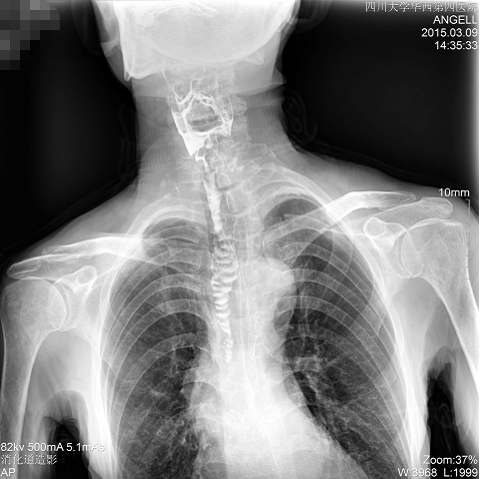

如下圖所示:該患者因吞咽時感到很難受,進食時也經常咳嗽故就醫診斷。華西醫院醫生使用動態DR為病人進行消化道造影診斷,要求他吞鋇后發現,食道各段通過順利,形態規則,雙側梨狀窩不對稱左側稍淺,多次吞咽動作后,仍見鋇劑滯留,并見鋇劑進入氣管,屬于會厭征陽性。會厭功能紊亂,鋇劑進入了氣管。

圖為正位:通過動態影像可以清楚看到鋇劑進入了支氣管道且雙側梨狀窩不對稱